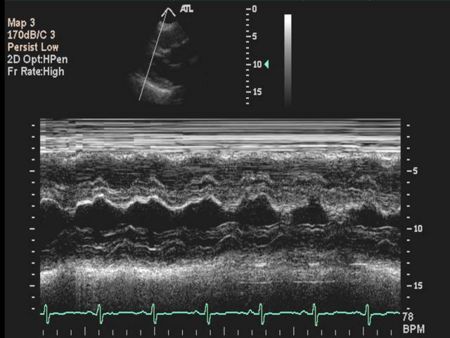

Ventricular M-mode

- Ventricular Wall Thickness

- Ventricular Chamber Size

- Intraventricular Masses